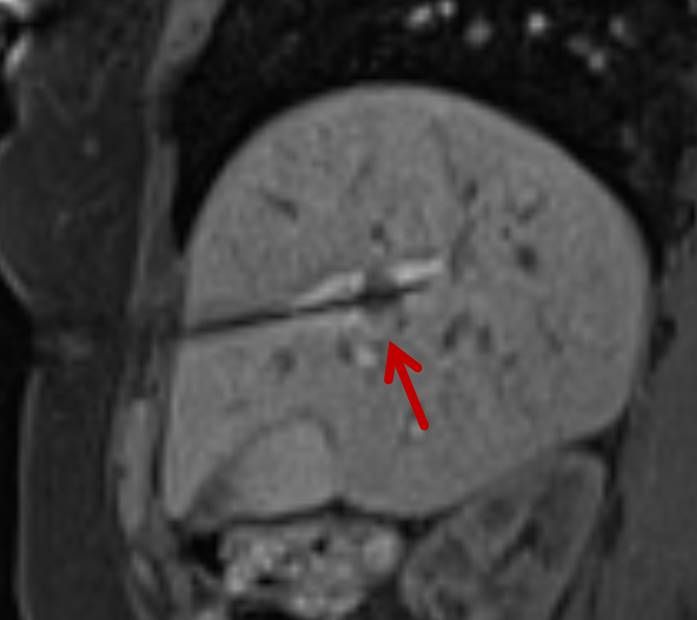

Die minimalinvasive Thermoablation ist auch eine Therapieoption für bestimmte Nierentumore. Damit ein Nierentumor mit einem thermoablativen Verfahren (Radiofrequenzablation oder Mikrowellenablation) effektiv und sicher behandelt werden kann, müssen bestimmte Bedingungen (wie Größe, Anzahl und Lage) erfüllt sein. Dies wird im Vorfeld des Eingriffes mit Kollegen der Urologie besprochen.

Bei der perkutanen Thermoablation von Nierentumoren werden spezielle Applikatoren unter CT- oder MRT Bildgebung in den Zieltumor eingebracht. Durch Hitze wird der Tumor zerstört.